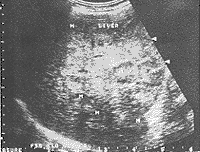

肝脏体积形态:本组病例肝脏体积均呈弥漫性增大。肝脏各条径线测量值均大于正常值。肝右叶上下径线>14cm为最明显。最长为18.9cm(图1)。因其随着肝癌细胞浸润时间长短不同,有时可表现为某段肝叶局限性弥漫增大,肝形态失常不规则。

图1 弥漫性肝癌

肝脏体积呈弥漫性增大,肝右叶上下径线多>14cm。肝包膜呈凹凸不平、波浪状改变,较圆钝。肝内回声结构紊乱,呈高、低回声不均匀分布。光点粗大,多呈弥漫分布高回声小结节,类似于“球状”,无包膜,无明显声晕。结节大小以3cm以下为主,极少超过5cm。很少见到融合成片,但后方多有轻度衰减现象。有时病变局限于某个肝叶段,而致肝脏形态不规则。肝内静脉变细,门脉管系走向均显示不清,并见血管绕行及中断现象。门脉主干直径>1.4cm以上,多伴有栓子形成。是诊断弥漫性肝癌的重要依据〔3、4〕。正常肝组织不易探及。若病变局限于某一肝叶段,其它肝叶组织可正常。同时伴有腹水、脾肿大、胆囊的改变。